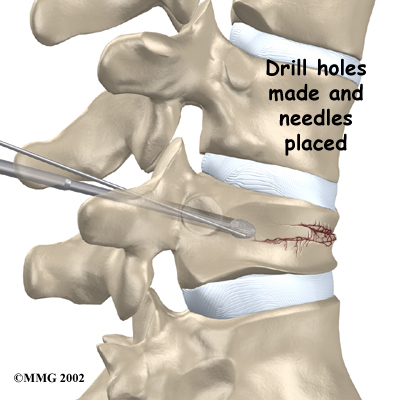

The patient lies on his or her stomach. To begin, the surgeon cleans the skin on the back with an antiseptic. Then the skin over the problem area is numbed using an anesthetic. Patients may also receive general anesthesia to put them to sleep during the procedure.

Two small openings are made in the skin on each side of the spinal column. Long needles are inserted through the openings. The needles are passed completely through the back of the spinal column into the fractured vertebral body. These needles serve as guides while the surgeon drills two holes into the vertebral body. The surgeon uses a fluoroscope to make sure the needles and drill holes are placed in the right spot. A fluoroscope is a special X-ray television that allows the surgeon to see your spine on a screen.

Drills Two Holes

The device works like a video, though the images are in the form of an X-ray. Metal objects show up clearly on X-rays. The needle is easy for the surgeon to see on the fluoroscope screen. This helps the surgeon know the needle goes into the correct spot.